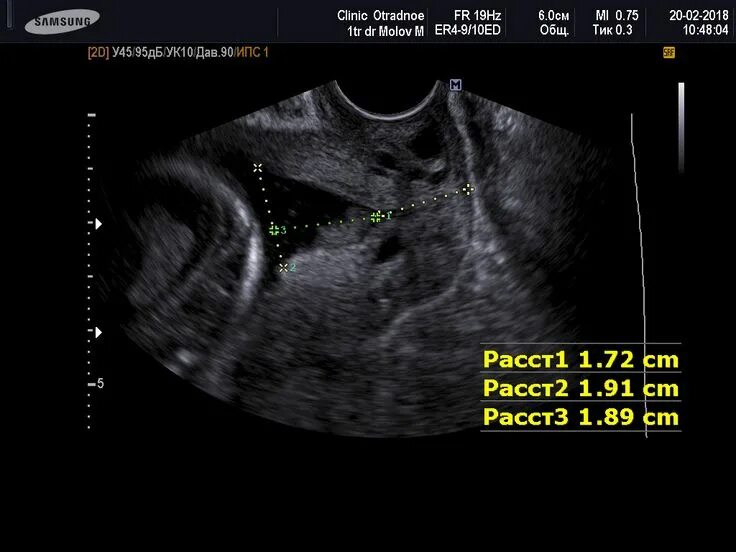

Зев т образный